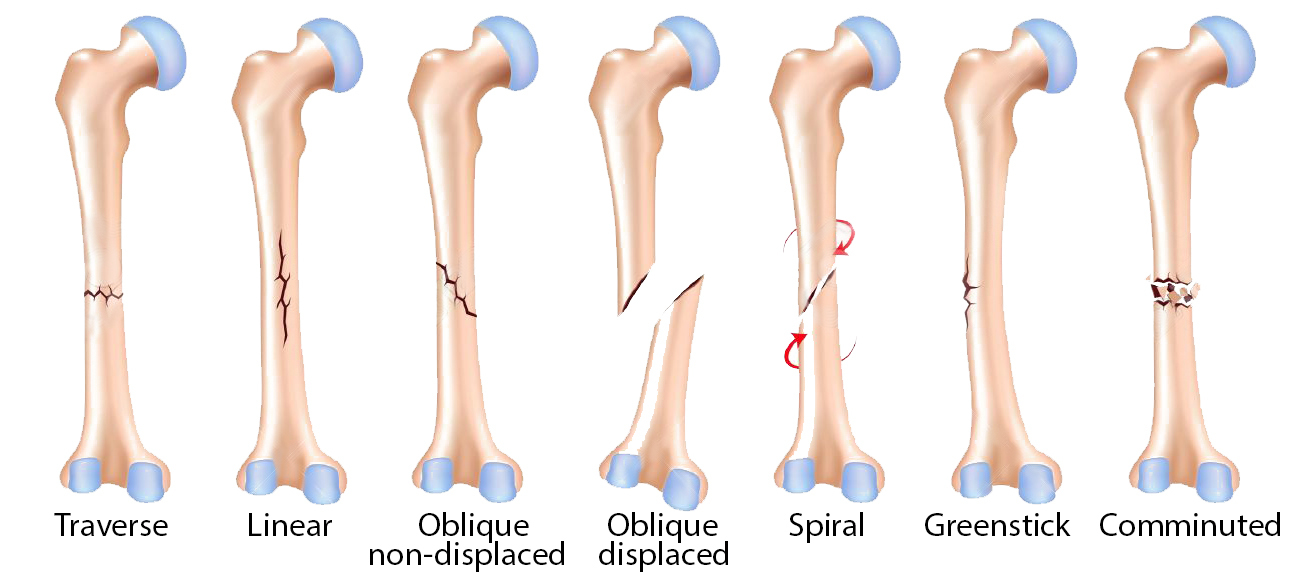

Describe the different types of fracture pattern